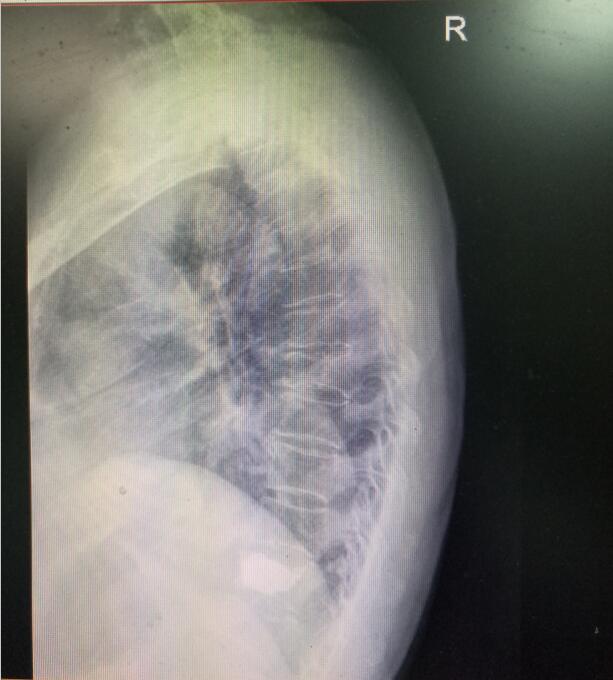

術(shù)前DR(數(shù)字化的x射線)

入院后第四天,由骨傷二科副主任楊陳一、劉永森醫(yī)生、唐國皓醫(yī)生聯(lián)合為患者成功實施了微創(chuàng)下的經(jīng)皮穿刺椎體后凸成形術(shù)。術(shù)后,患者腰背部疼痛逐漸緩解,術(shù)后第二天即下床活動。